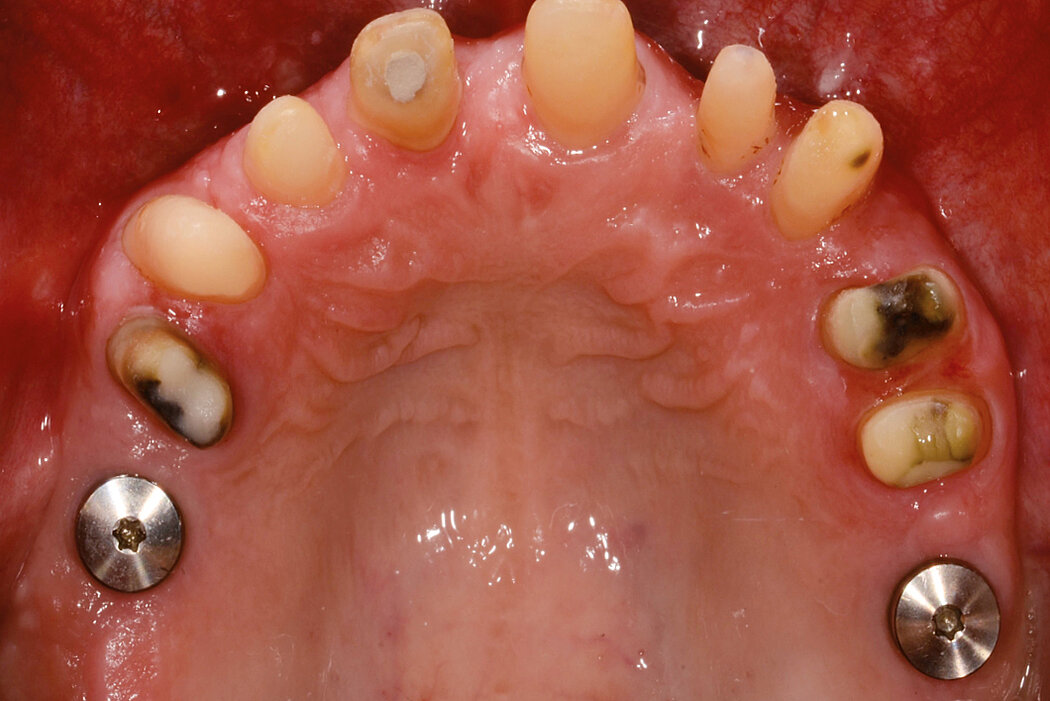

Ridge Preservation in multiple extraction sockets

Clinical challenge

In complex cases, I don’t want to experiment with materials. So I took here the proven Geistlich biomaterials.

Aim / Approach

Ridge profile maintenance under full arch bridge. Flapless procedure.